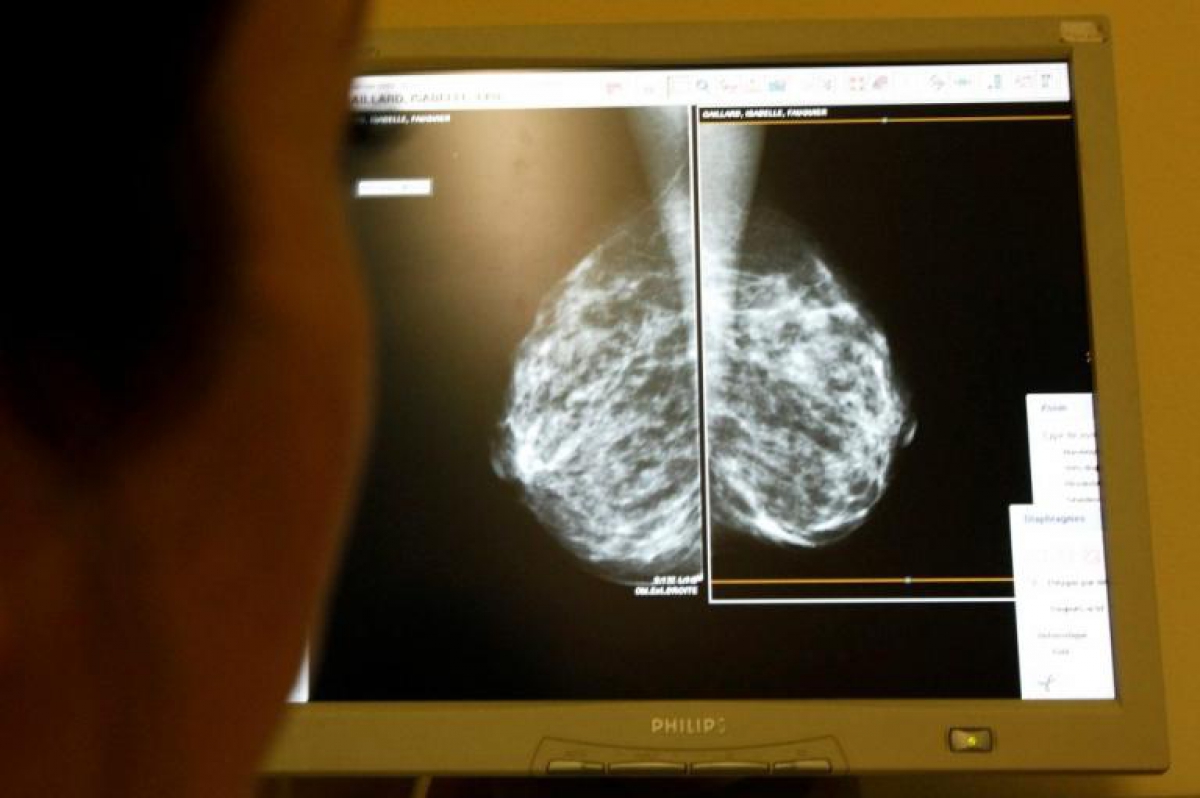

Ένα "λάθος" φαίνεται να έχει κοστίσει την ζωή σε 150.000 γυναίκες στην Βρετανία. Σύμφωνα με το BBC, 450.000 γυναίκες ηλικίας από 50 έως 70 ετών δεν πήραν ποτέ πρόσκληση από το βρετανικό εθνικό σύστημα υγείας για να κάνουν μαστογραφία.

Το σύστημα υγείας στην Βρετανία προβλέπει την αποστολή πρόσκλησης για μαστογραφία σε γυναίκες ηλικίας από 50 έως 70 ετών. Η πρόσκληση αποστέλλεται κάθε τρία χρόνια. Κι αυτό, γιατί η πιθανότητα να εμφανίσουν καρκίνο του μαστού αυξάνεται όσο περνούν τα χρόνια. Για το «λάθος» «καταδικάστηκαν» οι ηλεκτρονικοί υπολογιστές αλλά οι κακές γλώσσες λένε ότι μάλλον κάποιοι έβαλαν το χεράκι τους ώστε όσες από αυτές τις γυναίκες μπορούσαν να απευθυνθούν στον ιδιωτικό τομέα…